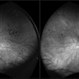

- Bilateral sclerosis of retinal vessles

- bilateral, retinal vessel

- Batchanaboina subba rao

- Optos widefield fundus camera

- Fundus photographs of an 71 -year-old women with bilateral sclerosed vessels s/p bilateral CRVO with PRP laser marks in the left eye. Known diabetic and hypertensive. Her visual acuity is good inspite of extensive sclerosis of vessles in both eyes - 20/30, N6 in the right eye and 20/80, N6 in the left eye.